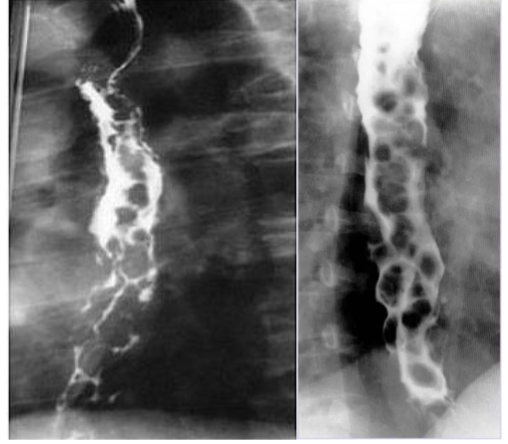

What is this and what type of scan

Varices, Barium swallow